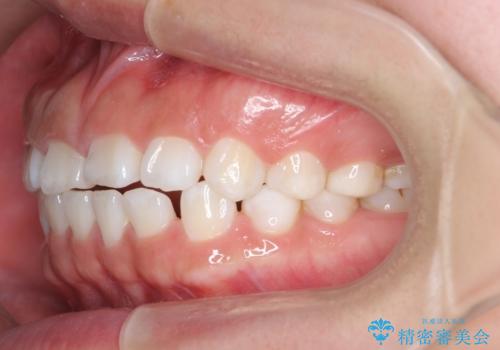

インビザライン 気になるすきっ歯の改善

- 上下顎前歯部の空隙が気になるので治したいと当院にいらっしゃった方の症例です。

非抜歯、インビザラインによる矯正治療により歯と歯の隙間および前歯の上下の隙間を閉じ切りました。